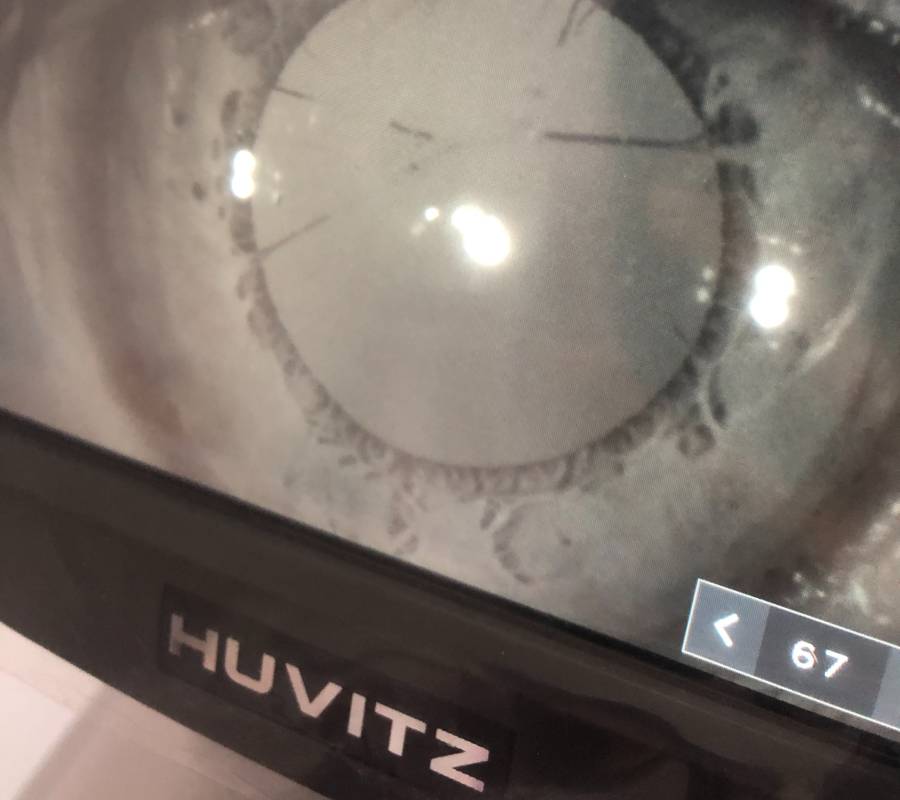

Pemeriksaan menyeluruh ke atas bahagian hadapan (anterior) dan belakang (posterior) mata—termasuk kornea, kanta, iris, retina serta saraf optik.